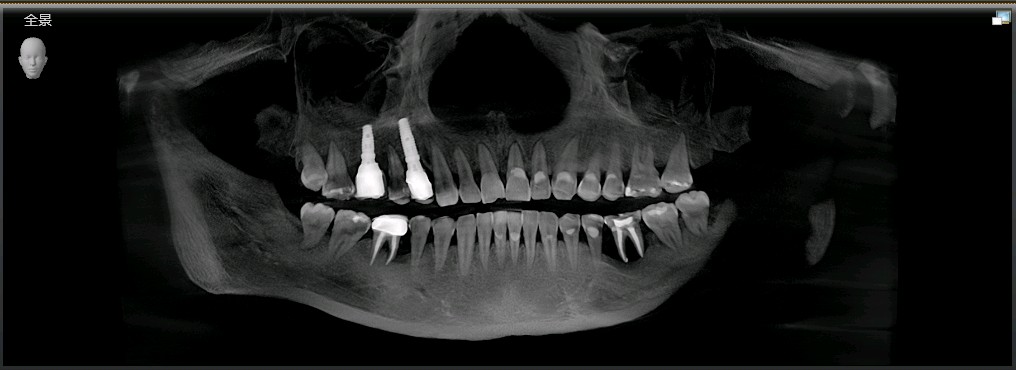

患者女,49岁,全口口腔卫生不良,结石++,牙槽骨水平吸收,附着丧失,可探及牙周袋。35,36,牙周-牙髓联合病变导致牙齿松动+++,根尖周阴影呈“烧瓶形”病变。

最终患者在做完牙周治疗后,拔除患牙。三月后植入ITI种植系统,植入骨粉骨膜及CGF膜严密缝合。术后骨结合良好。二期三期如期顺利进行,最终于今日安装牙冠,完成种植。患者满意。